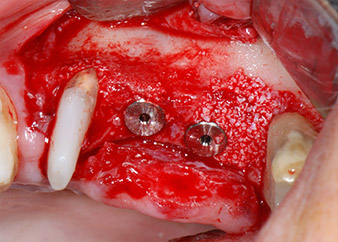

Low speed insertion of implant 26

Fig. 11: Low speed insertion of implant 26 with a torque limitation of 35 Ncm.

ready for the cover screws

Fig. 12: Both implants in place and ready for the cover screws.